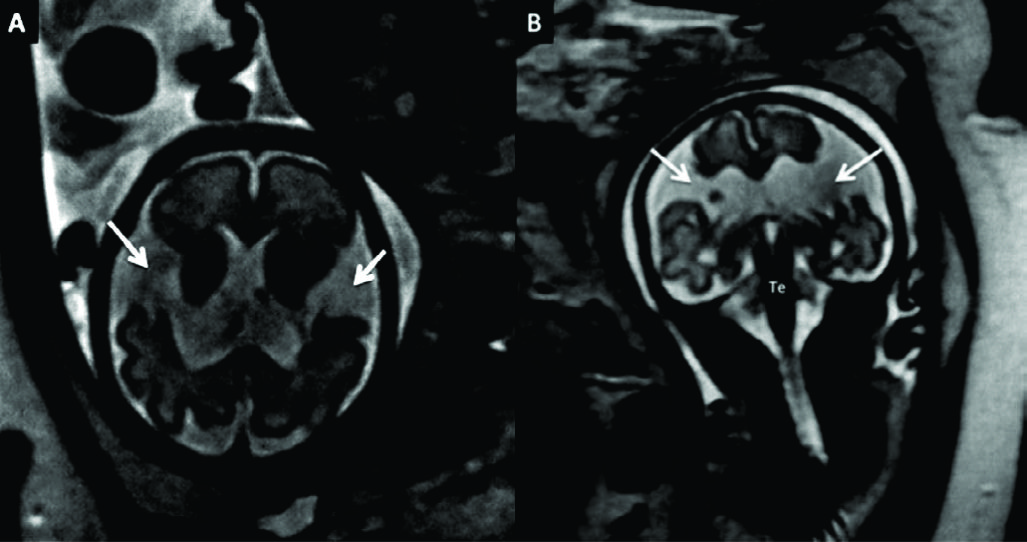

Figura 8

RM Fetal Esquizencefalia bilateral.

Estudio de RM realizado en la semana 29 con diagnóstico ecográfico de esquizencefalia bilateral. En el corte axial (A) y coronal (B) se reconocen las clásicas hendiduras que vinculan el sistema ventricular con el espacio sub-aracnoideo de la convexidad en ambos hemisferios.

Las estructuras de línea media son normales así como también el tronco encefálico (Te) y el resto de las estructuras intra-craneanas.

Figura 11